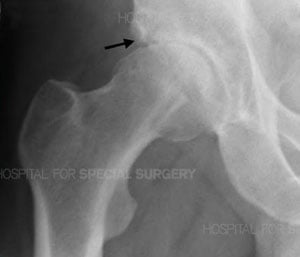

Anteroposterior (front-to-back) X-ray of a hip with osteoarthritis. The visible joint space narrowing at the top of the ball of the hip joint demonstrates cartilage has worn away. The arrow highlights sclerosis (bone thickening) and a cyst in the adjacent pelvic bone.